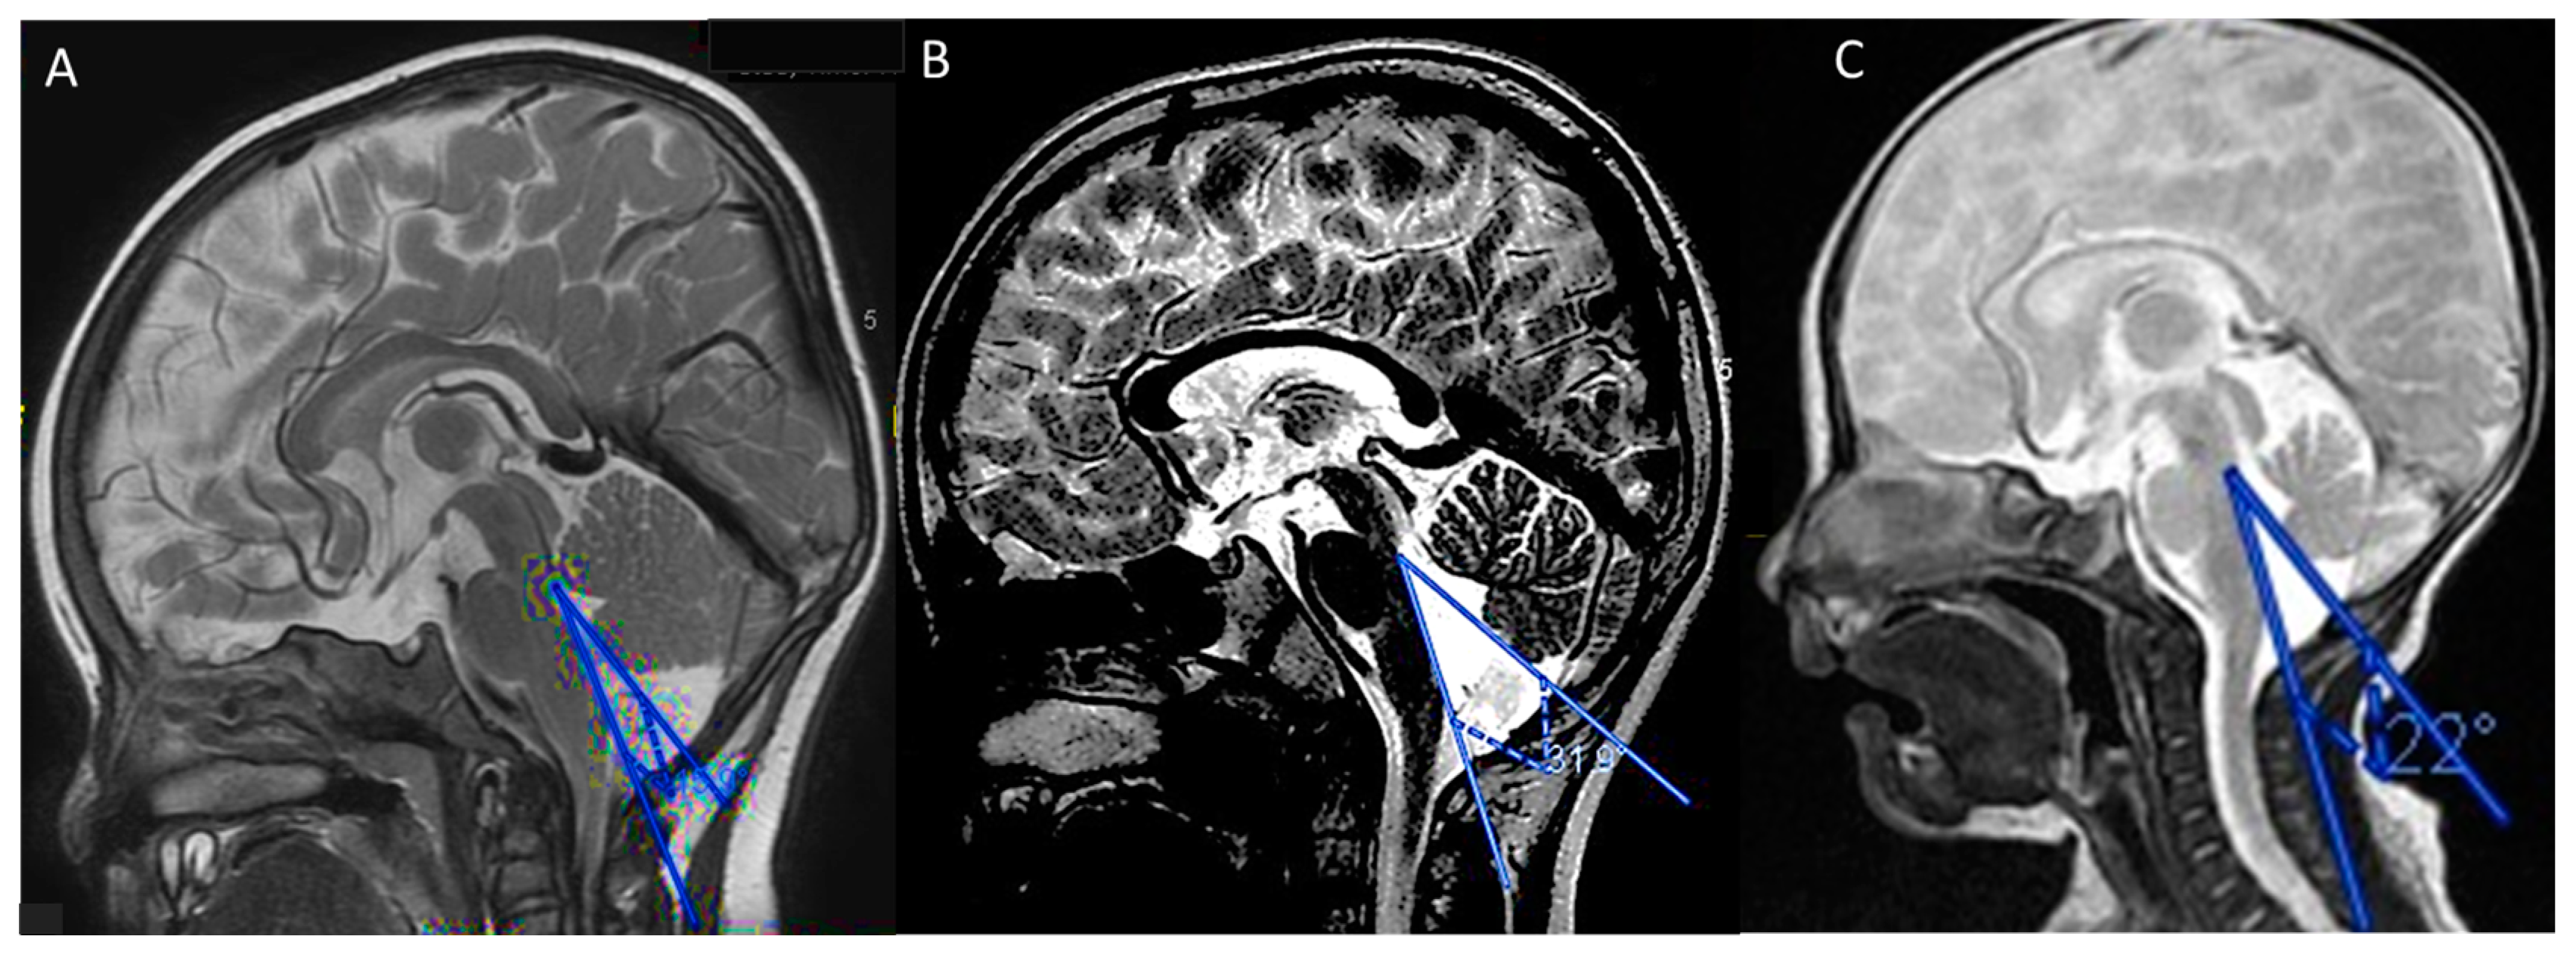

3.2.4. Neuroimaging Features